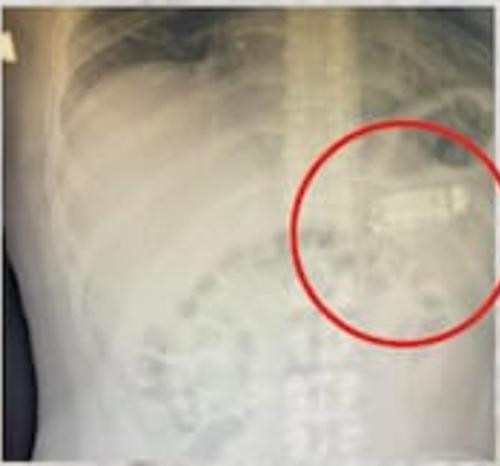

| Phim chụp cho thấy "vật thể lạ" trong cơ thể bệnh nhân. Ảnh: Skender Telaku. |

Bác sĩ Skender Telaku, người thực hiện việc lấy chiếc điện thoại ra khỏi bụng bệnh nhân, cho biết đây là một trong những ca phẫu thuật kỳ lạ nhất mà ông từng gặp trong sự nghiệp của mình. Telaku nói với truyền thông địa phương: “Tôi nhận được cuộc gọi, nói rằng có bệnh nhân nuốt một vật thể, nên chúng tôi chụp X-quang cho anh ấy và nhận ra rằng chiếc điện thoại đã bị rời thành 3 mảnh”.